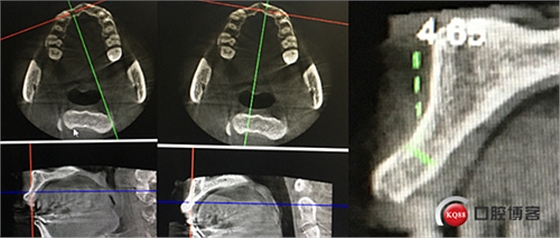

“以修復(fù)為導(dǎo)向”,在前牙種植體中心點(diǎn)就是未來(lái)牙冠舌側(cè)窩位置。那這個(gè)病例植體的方向和位置就只能是下圖右側(cè)這樣了。很明顯植體根尖部分要穿出唇側(cè)倒凹的。怎么辦?翻大瓣植骨蓋膜減張縫合?不!可以不翻瓣,大家仔細(xì)看看下圖右圖我畫(huà)的那條細(xì)細(xì)的弧線,是不是跟原來(lái)唇側(cè)凹陷的骨面成為左右對(duì)稱(chēng)的兩條弧,也就是說(shuō)骨膜從原來(lái)唇側(cè)凹陷骨面上剝離然后放到左側(cè)我畫(huà)的那條弧線那里根本不需要減張,這兩條弧線之間也就是唇側(cè)凹陷處放上骨粉,骨膜不會(huì)增加張力。不知道大家看明白了沒(méi)有。

設(shè)計(jì):1.僅做牙槽嵴頂水平切口,不做垂直切口,2.缺牙區(qū)由三顆牙改成兩顆牙,3.鄰牙冠延長(zhǎng)。